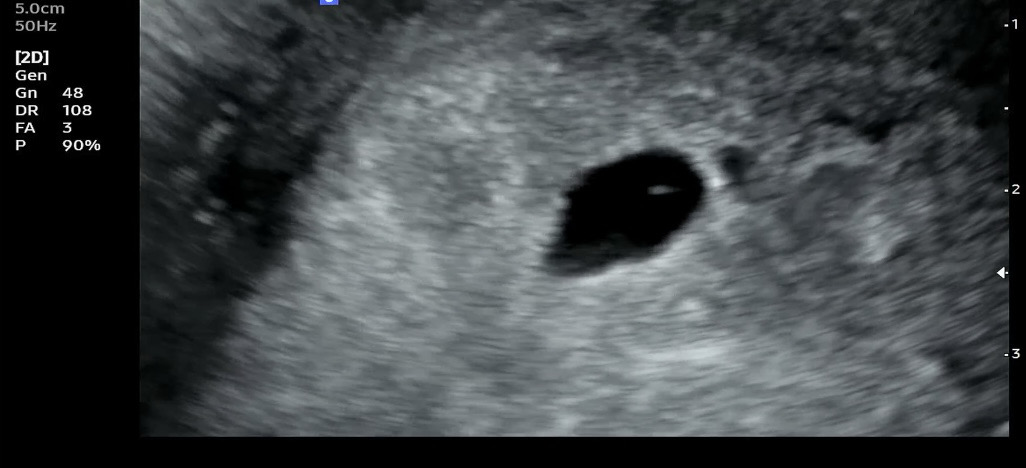

난황인지 아닌지 봐주세요 ㅠㅠ

6주 5일차로 심장소리 들으로 갔는데 난황이 안보인데요. 아기집은 1.38cm로 커져있었지만 고사난자 판정으로 그날 바로 소파술 하라는거 당황해서 저는 일주일 더 기다려본다고 한 상황입니다. 근데 초음파 보면 위치에 따라 보였다 안보였다 작아졌다 커젔다하는 점이 보이는데 주위에서는 난황같다하는데 그럼 의사는 왜 그거에 대해 말이없었는지 ㅠㅠ 우선 내일 다른 병원에 갈 예정입니다. 희망이 있을까요 ㅠㅠ 초음파도 봐주세요ㅠㅠ

난황 아닌 것 같아요 그리고 아기집이 1.38인데 저게 난황이라고 해도 너무 발달을 못해서 유산될 확률이 높지 않을까 싶습니다